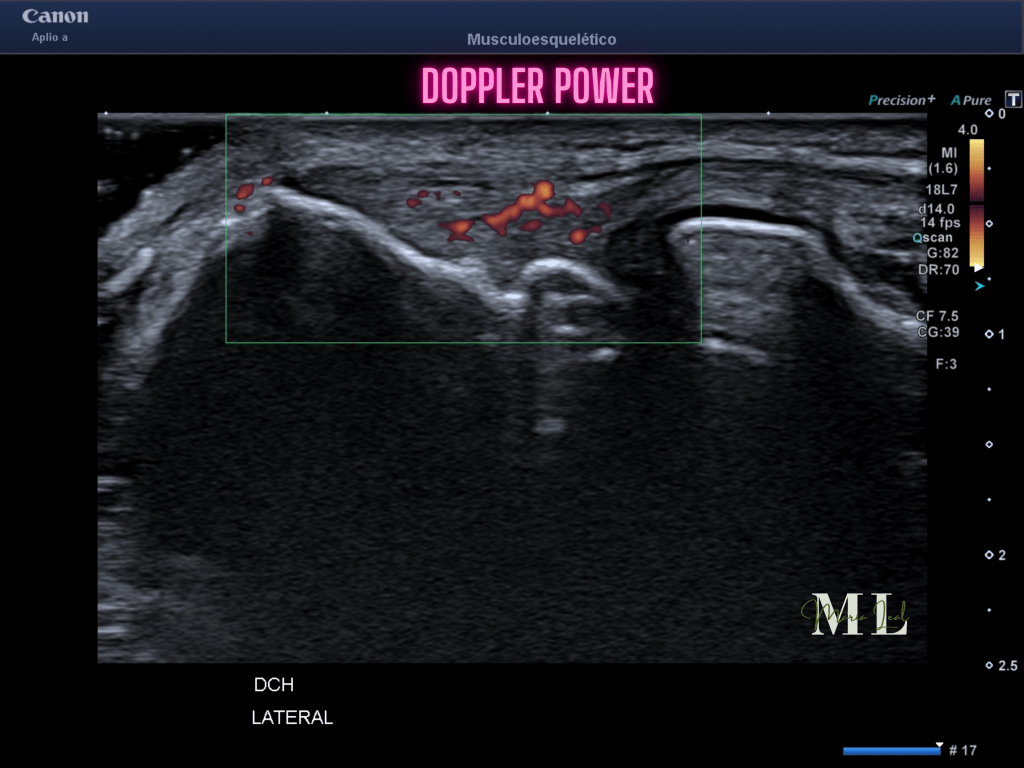

Con las imágenes que tienes arriba te explicamos las diferencias entre el Doppler y la SMI, que a su vez, tiene dos tipos, la normal, como un Doppler y la de Sustracción que es una imagen donde solo aparece el vaso.

- En casos de tendinosis, como la epicóndilitis, se ha observado una respuesta inflamatoria crónica que estimula el crecimiento de nuevos vasos sanguíneos en el tendón afectado.

- Estudios han demostrado que la neovascularización tendinosa puede estar asociada con dolor crónico y dificultades en la curación del tendón.

- Los nuevos vasos sanguíneos pueden llevar más sangre y factores inflamatorios a la zona, lo que aumenta la sensibilidad y el dolor.

- Aumento del flujo sanguíneo en la zona inflamada.